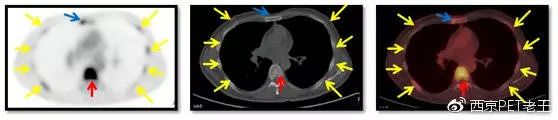

做完了PET/CT,我们先看看肝脏病变的情况(如下图):肝脏内和肝包膜区可见多个结节状、环状、条状葡萄糖代谢增高病灶(左侧列箭头),但CT图像上病变不明显(中间列),右侧列是PET/CT融合图像,不但能显示病灶的位置而且可以显示病灶的代谢情况。

从PET/CT图像上,我们判断为肝脏多发转移。除了肝脏,从图上我们还看到了多处骨头上有代谢增高,难道多个骨有转移?

患者肝脏病变的情况